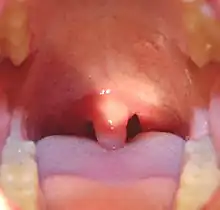

![]() Mouth of a child showing the uvula and swollen tonsils | |